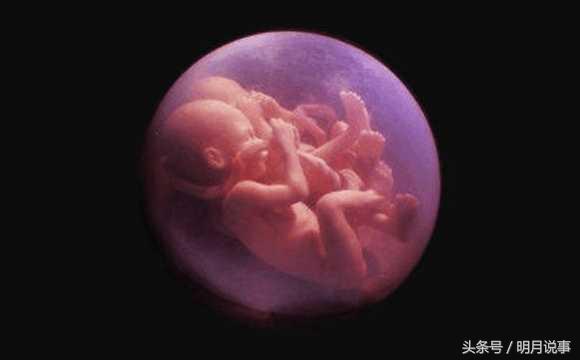

第一次做B超(7周)显示是一个孕囊,但9周时就变成两个了,同卵双胞胎还是很难得的!体检结果有胎心胎芽了,医生叫她在医院建了卡,NT检查预约在2月6号!